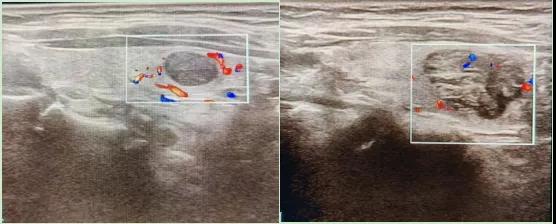

二、彩超如何“揪出”甲狀腺瘤?

彩超是一種無創(chuàng)、無輻射的檢查手段,被譽為甲狀腺的“高清攝像頭”。它的原理是:

超聲波探測:通過發(fā)射高頻聲波,生成甲狀腺的實時圖像。

彩色血流顯示:用紅藍色標記血流信號,區(qū)分腫瘤的供血情況。

醫(yī)生會通過以下特征判斷腫瘤性質(zhì):

1.形態(tài):良性多呈圓形,邊界清晰;惡性可能不規(guī)則、邊緣模糊。

2.回聲:低回聲結(jié)節(jié)風(fēng)險較高(像“烏云”一樣暗)。

3.鈣化:細小砂礫樣鈣化提示惡性可能。

4.血流信號:惡性結(jié)節(jié)常有豐富紊亂的血流。